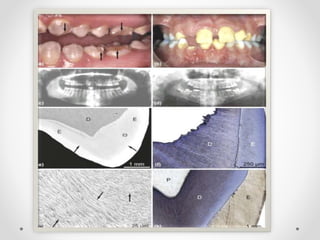

CLINICAL FEATURES:

Radiographic features :

- Full or partial obliteration of pulp camber and pulp canals

- Teeth have a bulbous crown , roots are narrower than normal ,

roots can also be short and blunt.

- Appearance of Shell teeth – presence of normal enamel thickness,

extremely thin dentin and enormous pulp chamber.

HISTOLOGICAL FEATURES:

-Enamel-normal appearance

-Dentin-irregular tubular dentin with large

areas of uncalcified matrix.

-Tubules are larger in diameter and lesser in

number.

 Both enamel and dentin appear very thin, pulp chamber

is extremely large- resulting in pale, wispy image of

tooth. Hence called GHOST TEETH.

 Marked reduction in radiodensity- teeth assuming a

ghost appearance.

 Short roots with open apices.

 Enlarged pulp showing pulp stones.

RADIOGRAPHIC FEATURES:

1. In the ground section- thickness of

enamel varies- resulting in irregular

surfaces.

2. Prism surface of enamel shows lack of

laminated appearance.

3. Dentin contains clefts through mixture

of interglobular dentin and amorphous

material.

4. Globular areas shows poorly organized

tubular dentin.

5. Pulp tissue contain pulp stones

exhibiting laminated calcification.